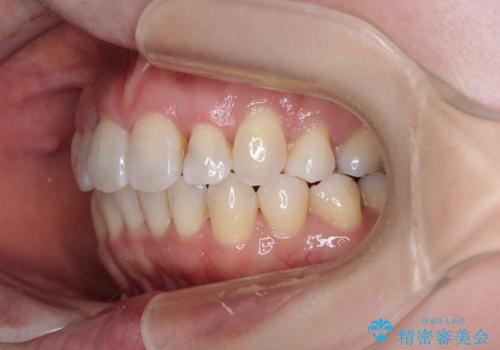

- 上下前歯のデコボコと、上顎の八重歯を気にして来院された患者様です。

下顎に対して上顎が前方にあり、第一大臼歯による咬合状態は上顎前突であったため、上顎のみ左右の第一小臼歯を抜歯し、ワイヤー装置にて矯正治療を行うこととしました。